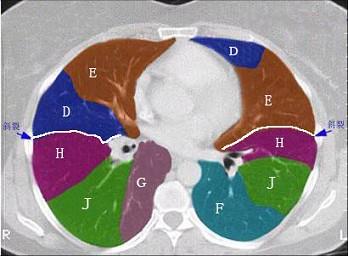

问题 结合肺段模式肺动脉干与右肺动脉层面(见图), 心室层面(见图), 主动脉弓层面(见图), 左右心房层面图(见图),选出左肺下叶的组成 ( )

选项 A、D+E+F+G+H+I+J B、C+D+E+F+G+H+I+J C、F +H+I+J D、E+F+G+H+I+J E、G+H+I+J

答案 C